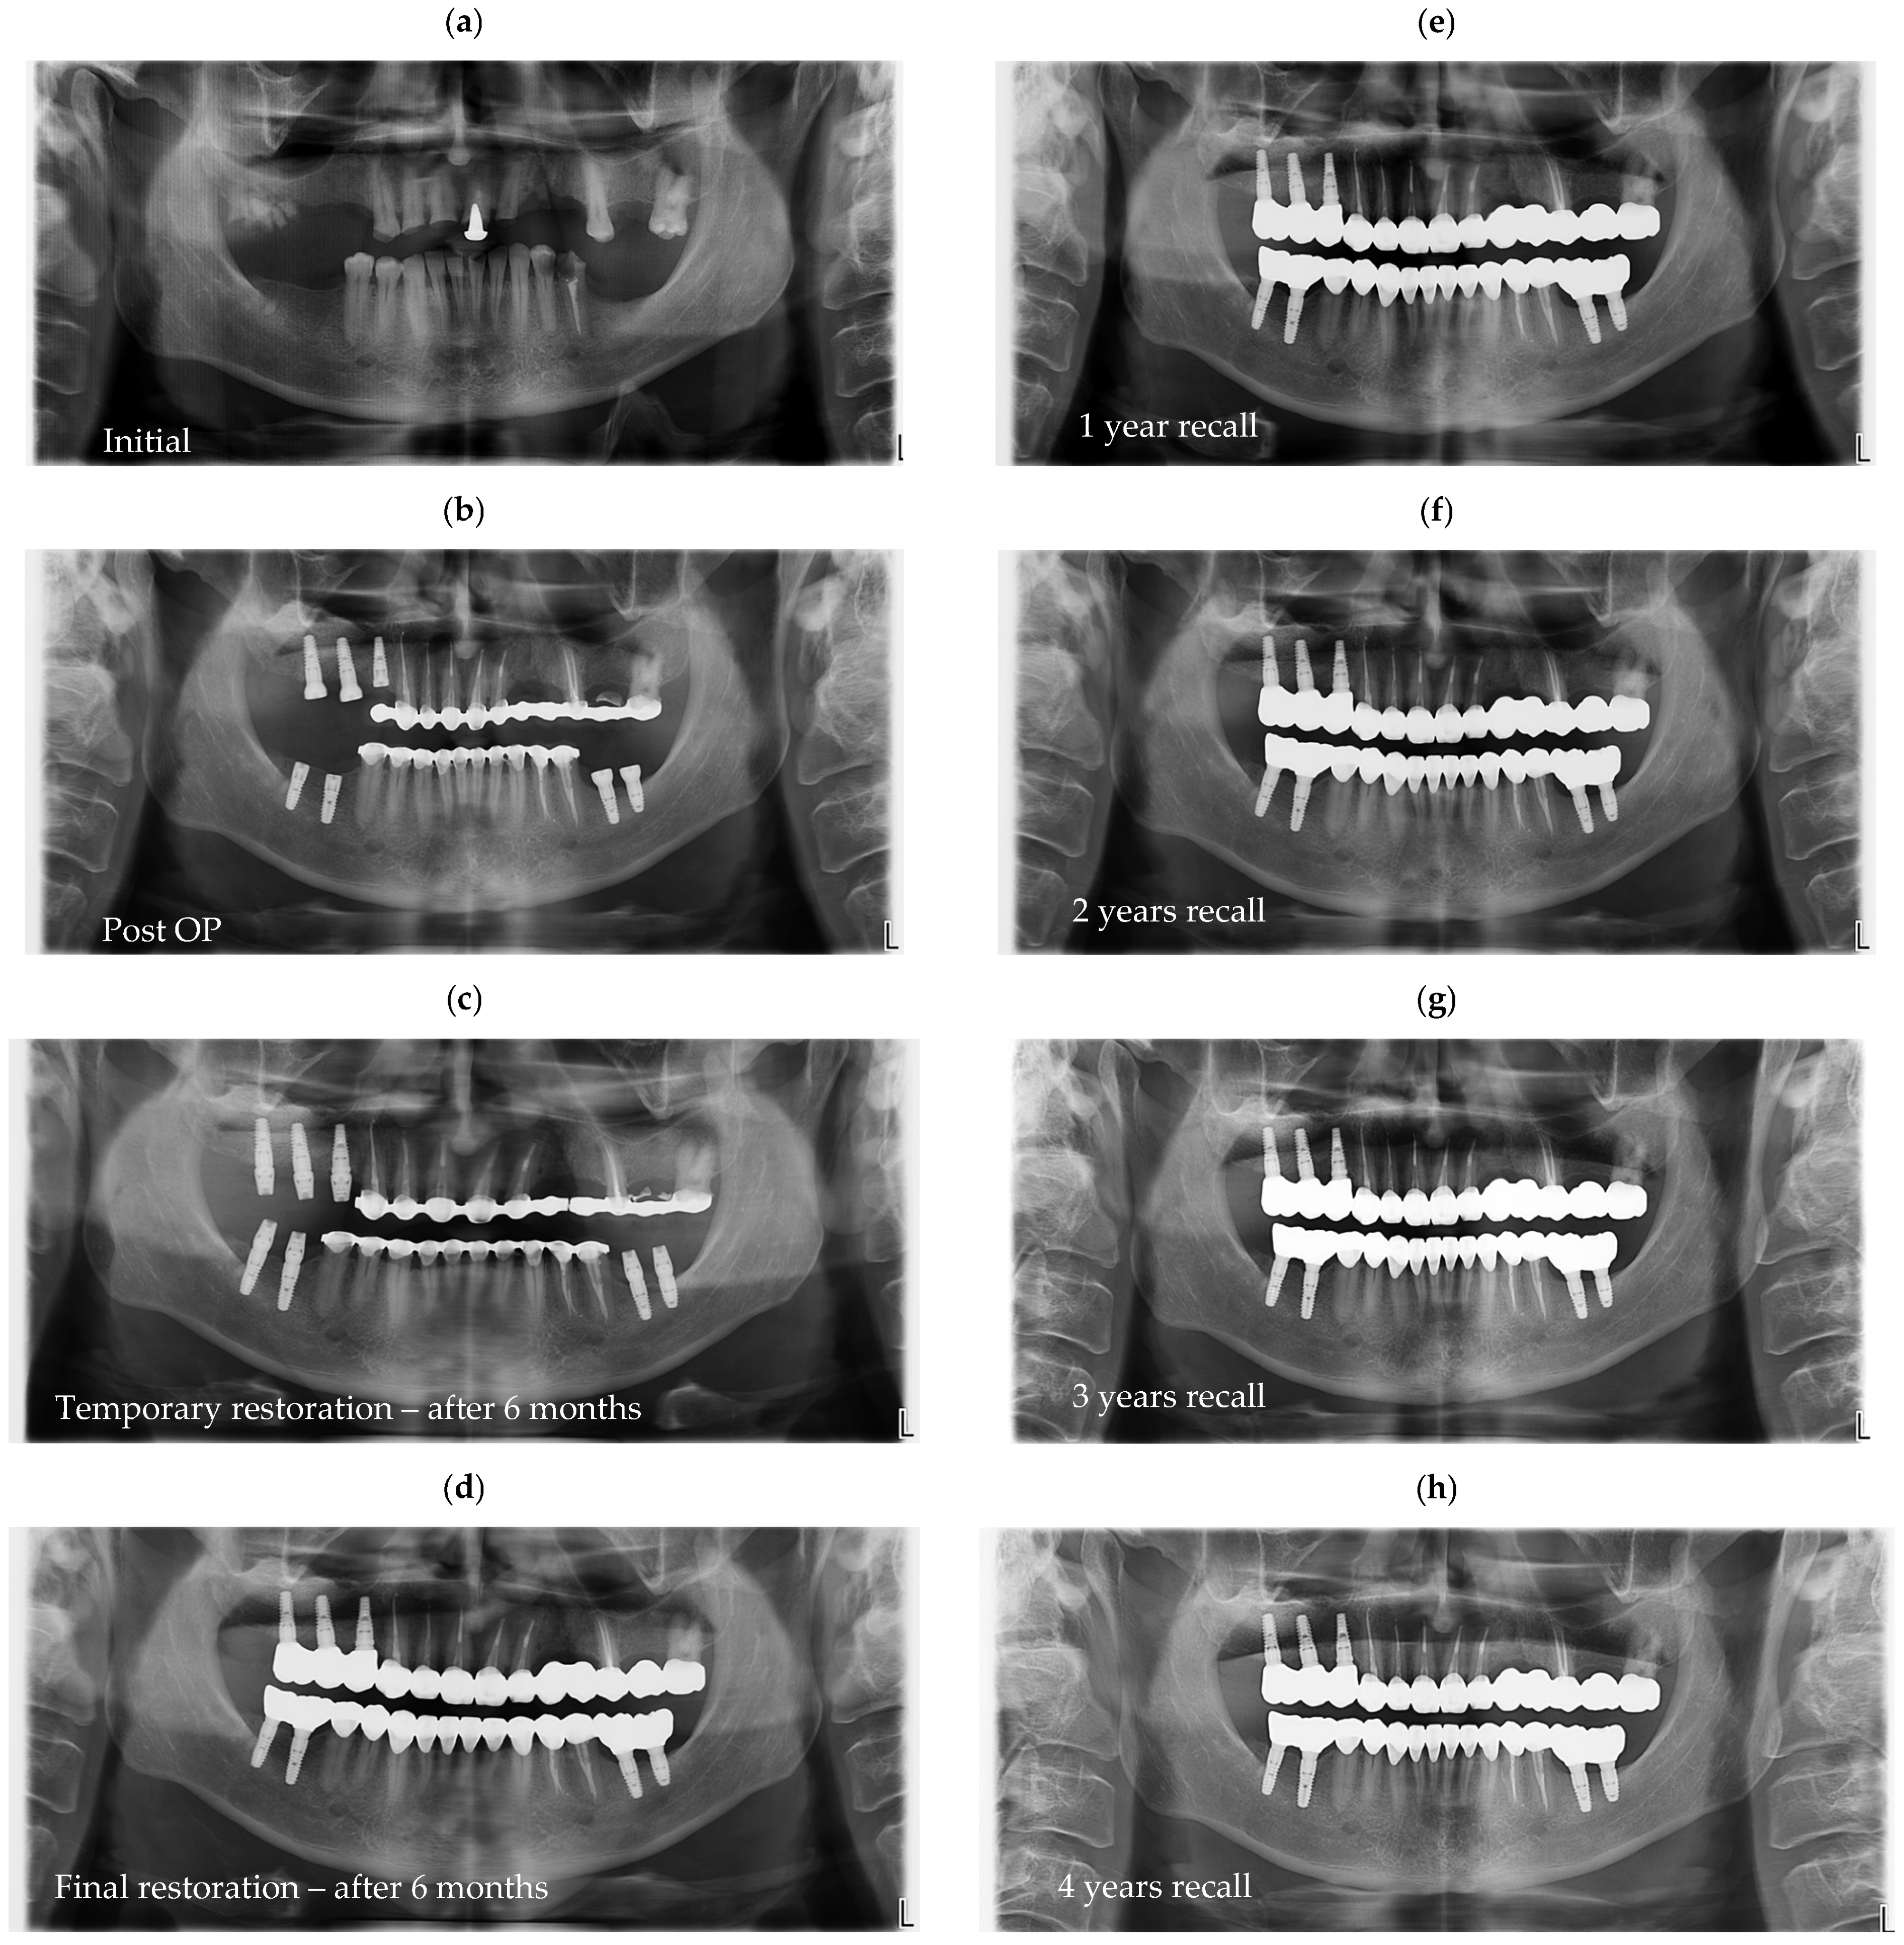

Radiographic assessments were conducted during the initial impression phase, provisional restoration try-in, and final prosthesis delivery. CBCT, panoramic radiographs, and intraoral periapical radiographs were used to visualize the implant–abutment interface and prosthetic fit. All imaging was performed using standardized exposure parameters, with radiographs analyzed using calibrated digital imaging software to assess marginal gaps and seating accuracy. In Figure 6, a representative case is presented, illustrating the radiographic sequence from the patient’s initial visit to the annual follow-up appointments. Figure 6a shows the panoramic radiograph (OPG) obtained at the first visit. Figure 6b corresponds to the postoperative image taken immediately after implant placement. Figure 6c illustrates the situation six months after surgery, following the delivery of the temporary restoration. Figure 6d shows the radiograph taken six months after provisional restoration was delivered, immediately after delivery of the definitive restorations. Figure 6e–i represent the annual recall examinations. Vertical marginal discrepancies were quantified as linear distances in millimeters (mm) at the implant–abutment interface. All radiographic examinations (periapical, panoramic, or CBCT) included in the analysis were obtained strictly for clinical diagnostic and follow-up purposes according to standard treatment protocols. No supplementary exposures were performed for research reasons. Data were analyzed retrospectively from existing clinical records. Impression procedure duration was recorded in minutes (min). Patient-reported outcomes were collected as Visual Analog Scale (VAS) scores on a 1–10 scale (dimensionless) (Appendix A). The same diagnostic criteria were applied across both digital and conventional groups to ensure consistency.

Quantitative comparison of marginal discrepancies was performed using radiographic measurements at the implant–abutment interface (Figure 7b). The presence of vertical gaps, angular misalignments, or overextensions was noted and compared between groups.

Figure 6. Representative panoramic radiographs obtained at different clinical stages of treatment. All radiographs were part of standard patient follow-up and were retrospectively analyzed; no additional exposures were performed for research purposes. (a) initial panoramic radiograph at the first visit; (b) postoperative image following implant placement; (c) six-month follow-up after surgery, at delivery of the temporary restoration; (d) radiograph taken six months after temporary restoration, immediately after delivery of the definitive restorations; (ei) annual recall examinations demonstrating stable peri-implant bone levels over time.

Figure 7. OPGs of (a)—case with a perfect fit and (b)—case with misfit of 0.7 and 0.5 mm on implants from position 3.6, respectively, 3.7.